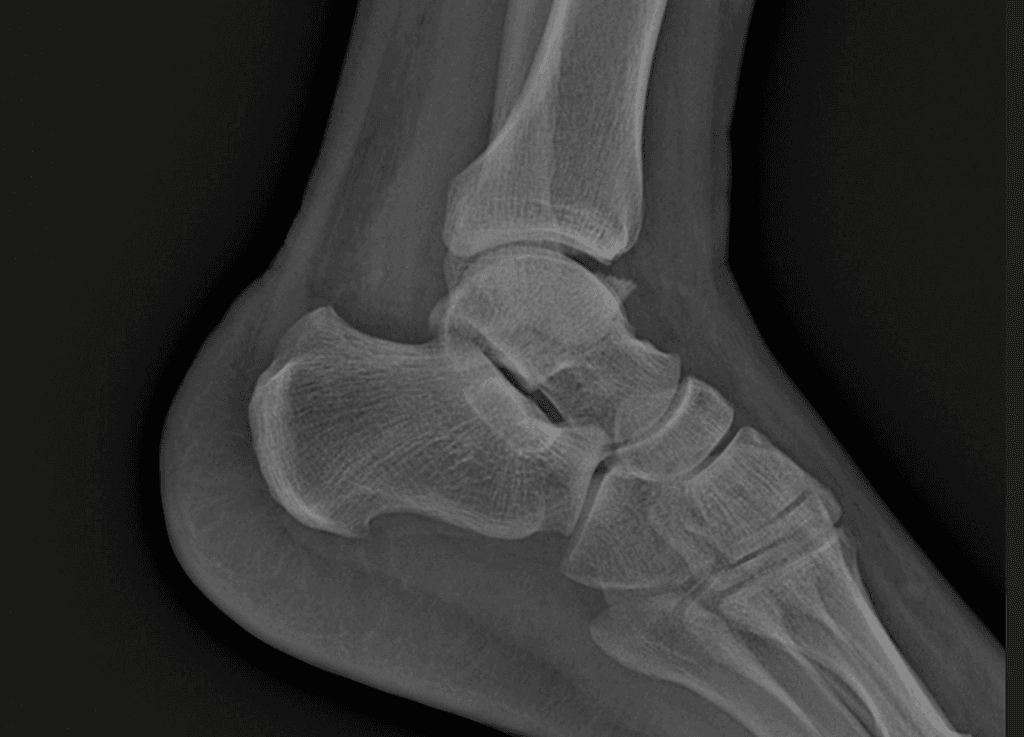

Lipohaemarthosis (dịch mỡ - máu trong khớp)

- "Lipohaemarthrosis là dấu hiệu đặc hiệu của gãy xương dạng khớp, thường do gãy plateau chày, khi mô tủy chứa mỡ tràn vào khoang khớp."

- "Sự xuất hiện của mức dịch - mỡ trên X-quang gối nghiêng ở bệnh nhân chấn thương gợi ý lipohaemarthrosis và cần đánh giá thêm bằng CT hoặc MRI."

Lipohaemarthrosis là tình trạng có cả mỡ và máu trong khoang khớp, thường gặp nhất ở khớp gối sau chấn thương. Nó xảy ra khi một gãy xương dạng khớp làm vỡ khoang tủy xương, cho phép mỡ tủy tràn vào khoang hoạt dịch, tạo nên mức dịch - mỡ đặc trưng trên X-quang nghiêng khi bệnh nhân nằm nghiêng hoặc tia ngang. Nguyên nhân phổ biến nhất là gãy plateau chày, mặc dù các gãy xương dạng khớp khác như gãy đầu dưới xương đùi hay xương bánh chè cũng có thể gây ra hiện tượng này. Việc phát hiện lipohaemarthrosis rất quan trọng vì nó gợi ý một gãy xương ẩn không nhìn thấy rõ trên X-quang ban đầu. Cần chụp CT hoặc MRI để đánh giá đầy đủ kiểu gãy và tổn thương mô mềm. Điều trị phụ thuộc vào mức độ di lệch, tính ổn định và tổn thương đi kèm, từ bất động đến cố định phẫu thuật.